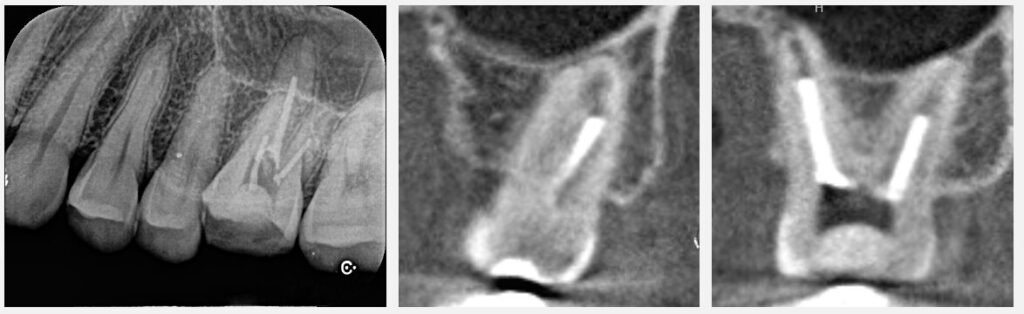

痛みに関しては、治療後すぐに消えることもあれば、すぐにスッと軽減することもあれば、6〜12ヶ月かけて徐々におさまることもあります。また、治療を終えた後は硬いものを噛むことは避け、意図的に指で触ったりすることもしないようにお願いします。また、根管治療は確かにやり直しをすればするほど残っている歯が薄くなったり、問題が起こる可能性はあります。しかし、現状では、ラバーダムが装着されていない、根管治療後のレントゲンを見るともう少し綺麗にできそうな感じがある、という点から、再治療が第一選択となるでしょう。

この患者様の症例はこちら:根管治療が終わったばかりだが、痛みが続いておりもう一度根管治療のやり直し言われた【50代女性】_症例37